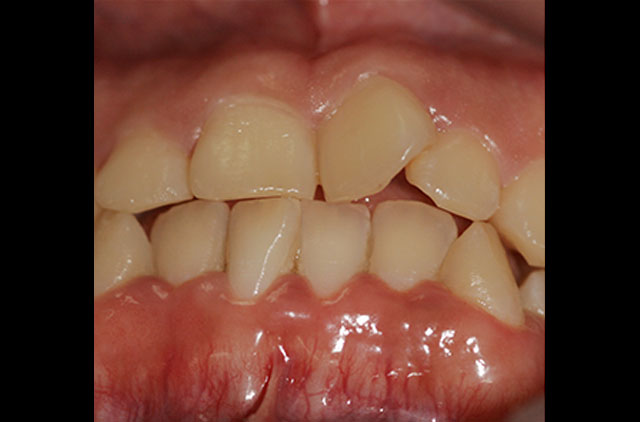

Fotografía Intra y Extra Oral

-Fotografía Clínica Digital (10 Tomas)

-Tomas Adicionales